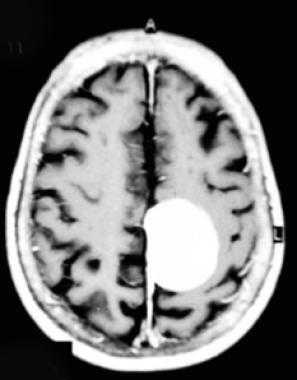

Парасагиттальная менингиома на МРТ с контрастным усилением. Видно гомогенное округлое образование, активно накапливающее контрастное вещество.